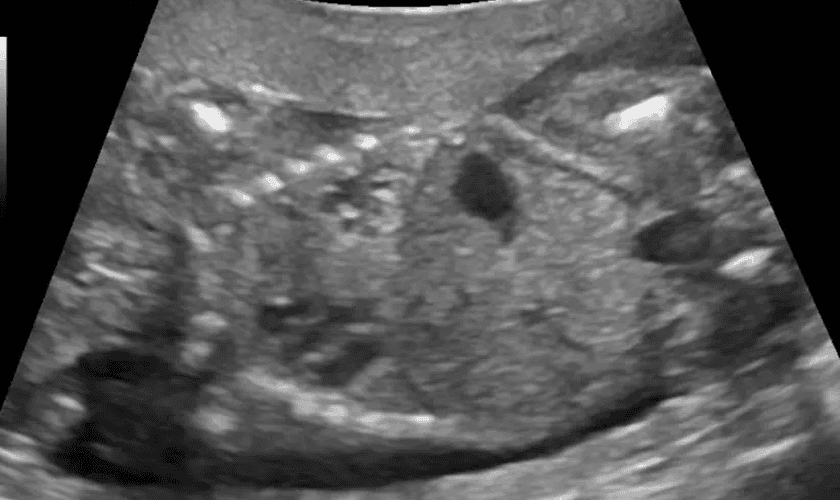

A conduta médica que consiste na injeção de determinados agentes farmacológicos, como injeção de cloreto de potássio ou de digoxina, aplicadas diretamente no coração do feto, causando parada cardíaca imediata. Após o coração parar de bater, o feto é retirado da barriga da mulher para completar o procedimento do aborto.